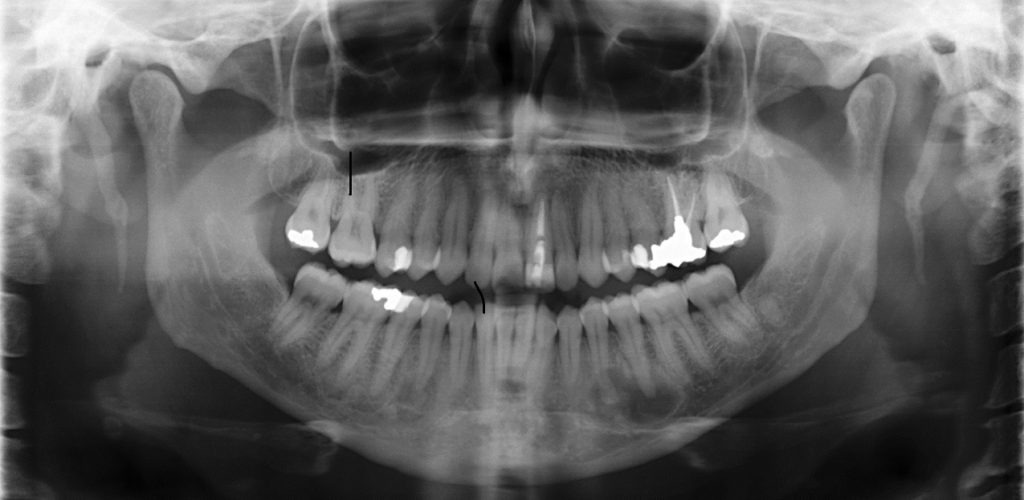

Περιστατικό 2

Γυναίκα 45 ετών, λευκής φυλής. Παρατηρούνται μικτές περιακρορριζικές αλλοιώσεις στην κάτω γνάθο αμφοτερόπλευρα.